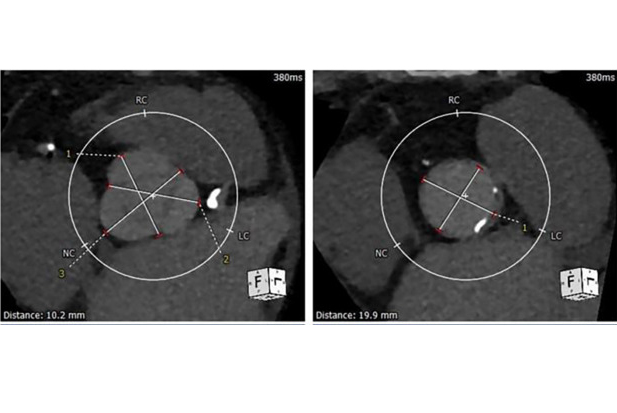

Cardiac CECT localizes fatty tissue in heart